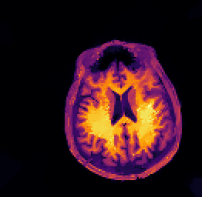

Figure 5: PET reconstructions with structural MR side information. Filtered back-projection (FBP) and TVTV\operatorname{TV} do not correct motion and yield poor reconstructions. Both the three-step and the proposed method correct the deformation and the reconstruction satisfyingly agrees with the ground truth. We give SSIM and RD values of the reconstructed images and deformation parameters. For FBP and TVTV\operatorname{TV} no deformation was corrected and SSIM is given with respect to the deformed ground truth.

The sinogram data and the deformed image which was used to generate the data are shown in the top row of Figure 5. Furthermore, we show the side information and the ground truth image. In the second row of Figure 5 we show four different reconstructions: the first one obtained through filtered back-projection, the second one utilizing TVTV\operatorname{TV} regularization, the third one using the three-step method (22), and the fourth one being the proposed method. The first two methods, which do not use the side information or correct any motion, exhibit poor image quality due to strong noise in the sinogram. On the other hand, both the three-step and the proposed method correct the deformation and the reconstructions are in very good agreement with the ground truth image.

Quantitatively, the SSIM values for filtered back-projection and TVTV\operatorname{TV} are relatively low whereas they are comparably high for both the three-step and the proposed method, with slightly better values for the proposed method. The same is also true for the relative errors of the computed deformation fields.